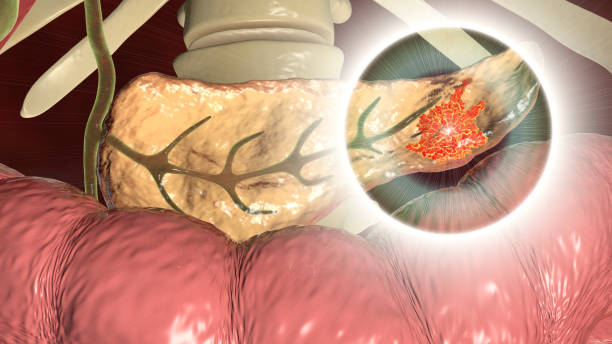

췌장암 초기증상 어려운 발견

췌장암은 정말로 발견이 어려운 질병 중 하나입니다. 복부 초음파는 일반적인 검사법 중 하나이지만, 췌장이 복부 내에서 깊숙하게 위치해 있어 잘 보이지 않는 경우가 많습니다.

또한, 일부 환자에서는 췌장암이 아닌 것처럼 보이는 경우도 있습니다. 따라서 복부 초음파로는 췌장암을 정확하게 발견하기 어렵습니다.